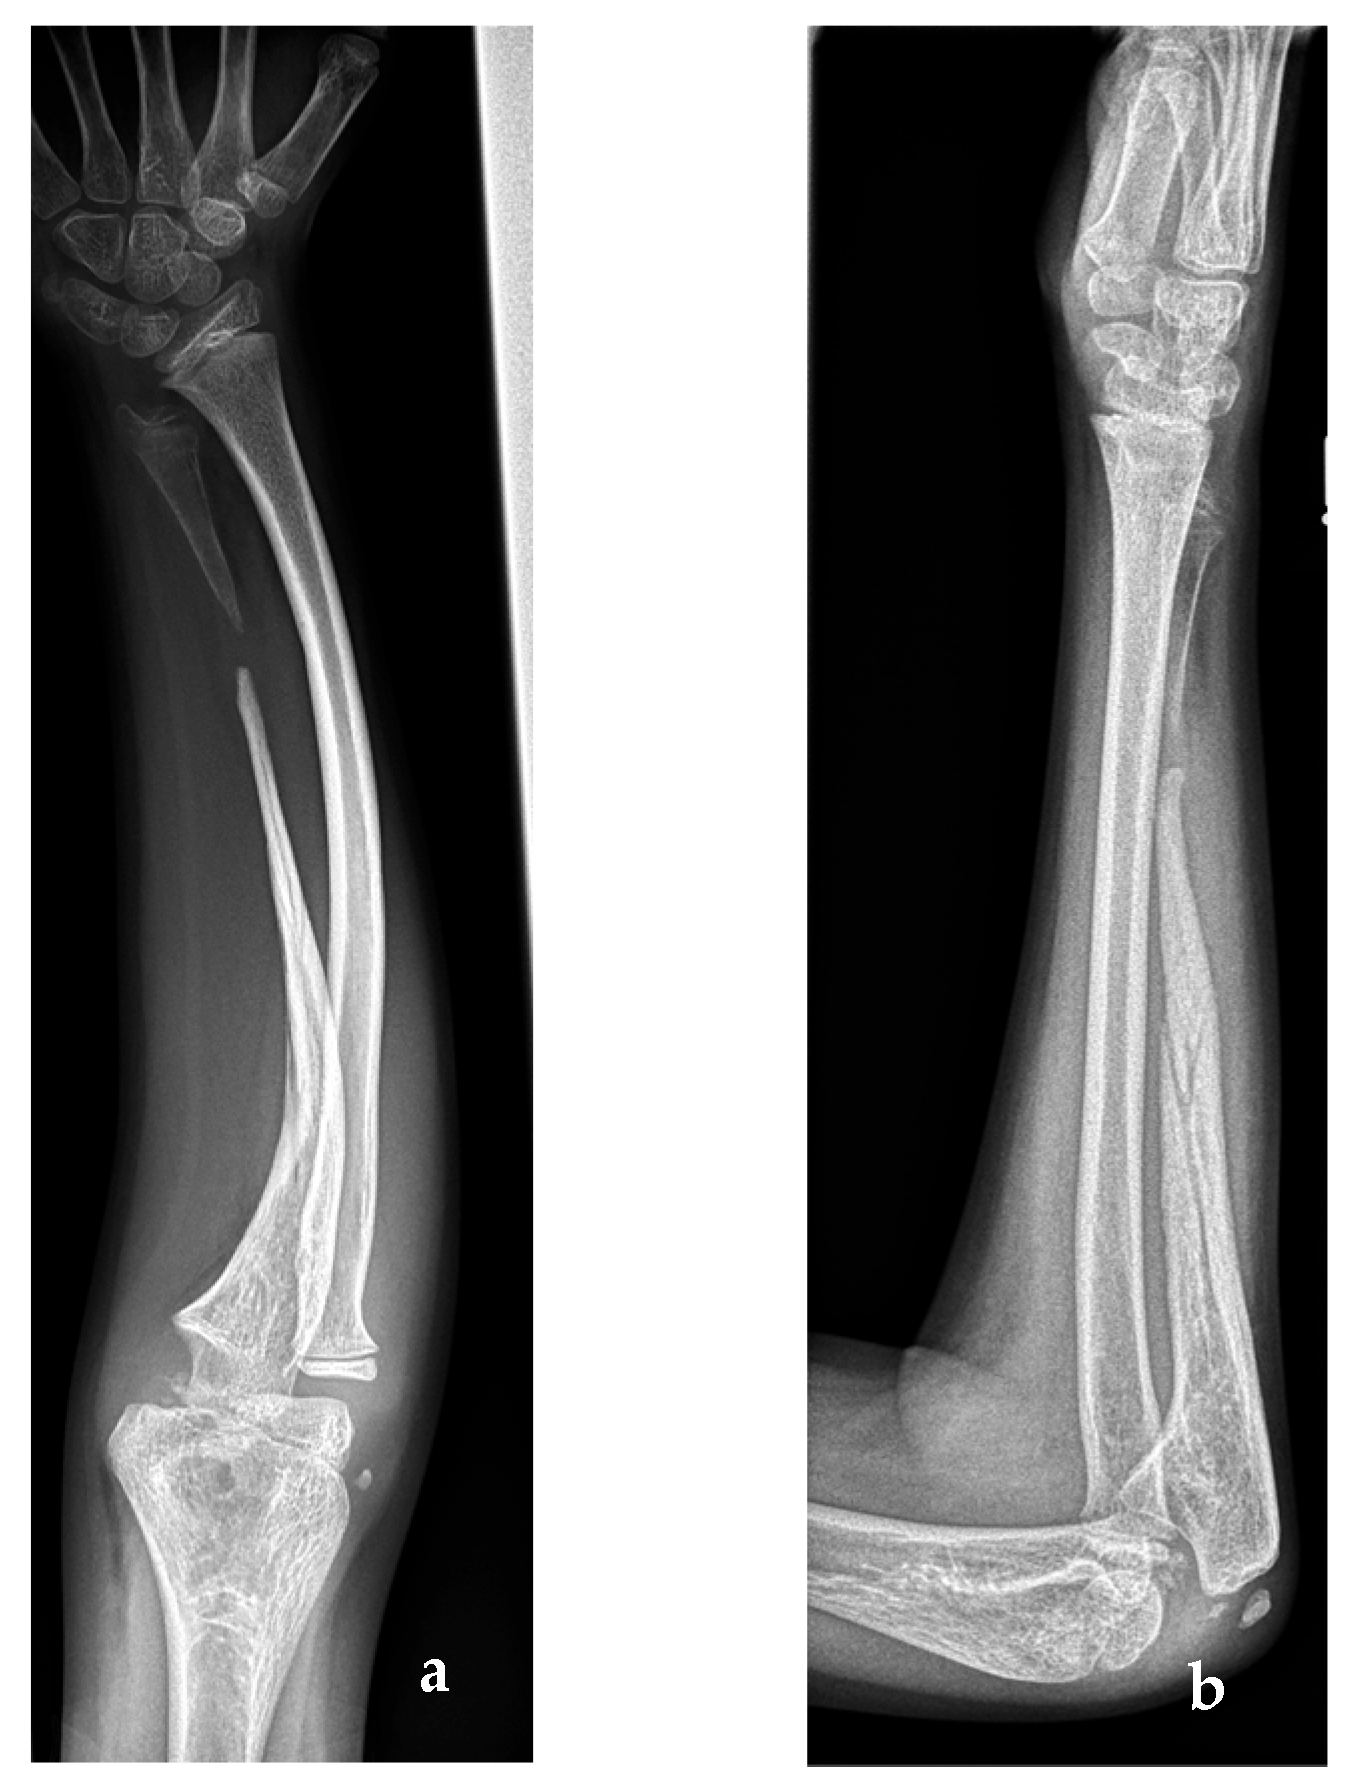

2. Case Report

2.1. Case Report